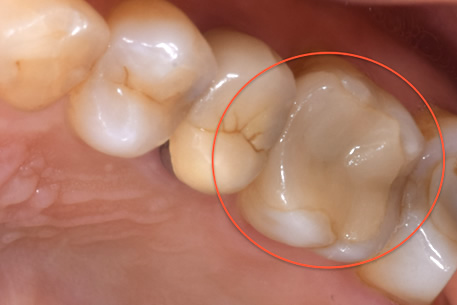

症例① セラミックインレー

治療前

治療後

年齢 60代女性

主訴 歯がしみる

治療方針 つめ物がすでに入っている歯です。そのため、見た目では虫歯があるかどうかわかりませんでしたので、レントゲンを撮影しました。すると、つめ物の中で虫歯になっていることがわかりました。虫歯は、とても大きくなっており神経に近い部分まで進行していました。

治療内容 神経が保存できるかどうか経過をみるために、覆罩といって、神経を守るための処置を行いました。2ヶ月ほど経過を見て、症状が出ないことを確認して、つめ物の型をとり、つめ物をいれていきました。

治療期間 3ヶ月

リスク・副作用 治療後に冷たいものがしみるなどの症状がでることがあります。つめ物を入れた後に痛みなどの症状が出てしまう場合は神経を取り除く治療が必要になります。

費用 ・セラミックインレー:55,000円(税込)

見た目では全くわかりませんが、レントゲンでは黒く抜けて虫歯になっていることがわかります。

治療中①:つめ物をとったところ。茶色い部分は虫歯になっている。

治療中②:染色液を用いて虫歯を選択的に取り除いた。歯はかなりなくなっており、神経近くまで進行していた。

経過観察

虫歯を取り除いた後、神経を守るためのお薬をつめて、2ヶ月ほど経過観察をした。

経過観察中に症状がでなかったため、セラミックのつめ物をいれていった。